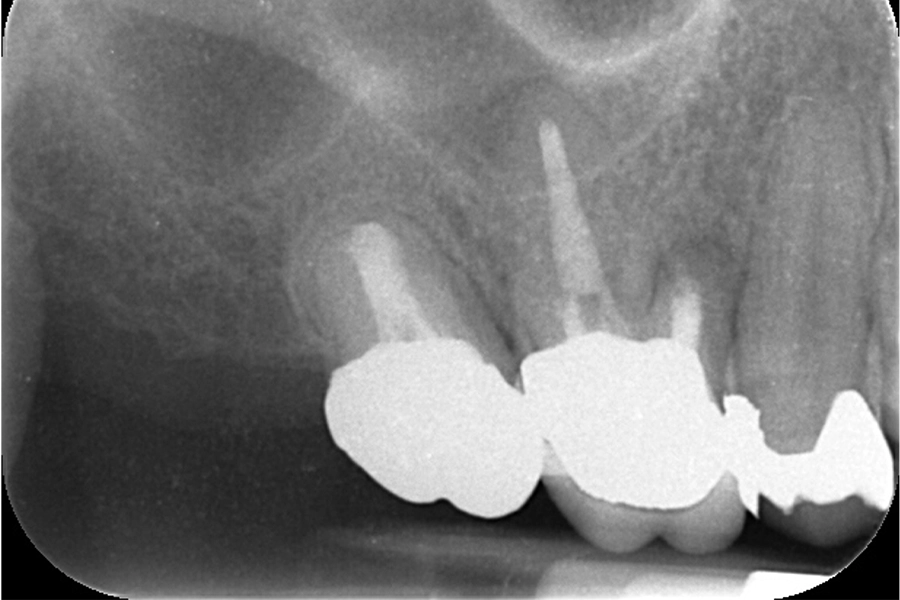

治療前